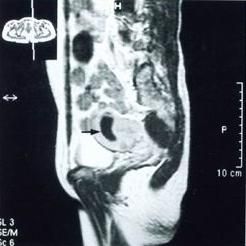

宮角妊娠透視觀察血管性介人治療套用於宮角妊娠的病例較少,其治療方法與宮頸妊娠相似。

宮角妊娠側面透視血管性介入治療

血管性介人治療套用於宮角妊娠的病例較少,其治療方法與宮頸妊娠相似。